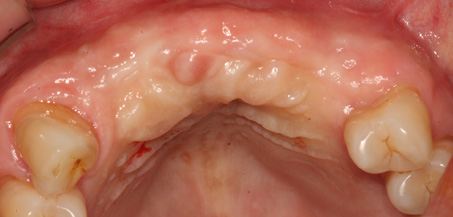

상악동 거상술

상악동 거상술 고난이도 뼈이식술 입니다.

청담네오플란트에서는 상악동 거상술을 비롯한

고난이도 임플란트 시술 노하우가 풍부한 치의학 박사

전문의가 직접 상악동 거상술을 시행합니다

상악동은 윗턱뼈 내부의 구조물로서 개개인에 따라 생김새가 다릅니다.

상악동의 바닥이 잇몸뼈 방향으로 많이 내려온 경우, 임플란트를 식립하기에

잇몸뼈가 부족하게 됩니다. 이러한 경우 상악동 내부로 뼈이식을 하는

상악동 거상술이 필요하게 됩니다.